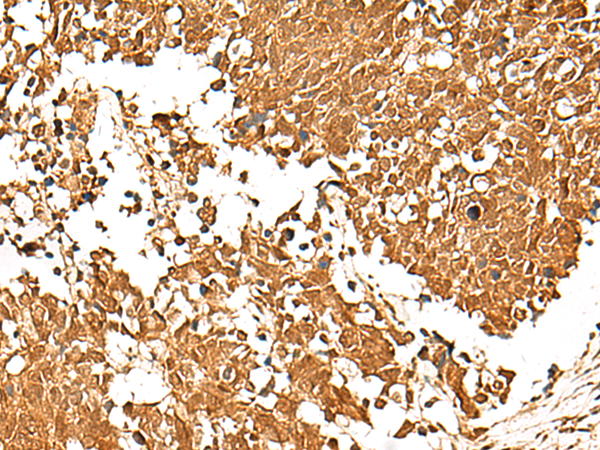

分类: 科研抗体货号: P04254别名:应用: IHC反应种属: Human